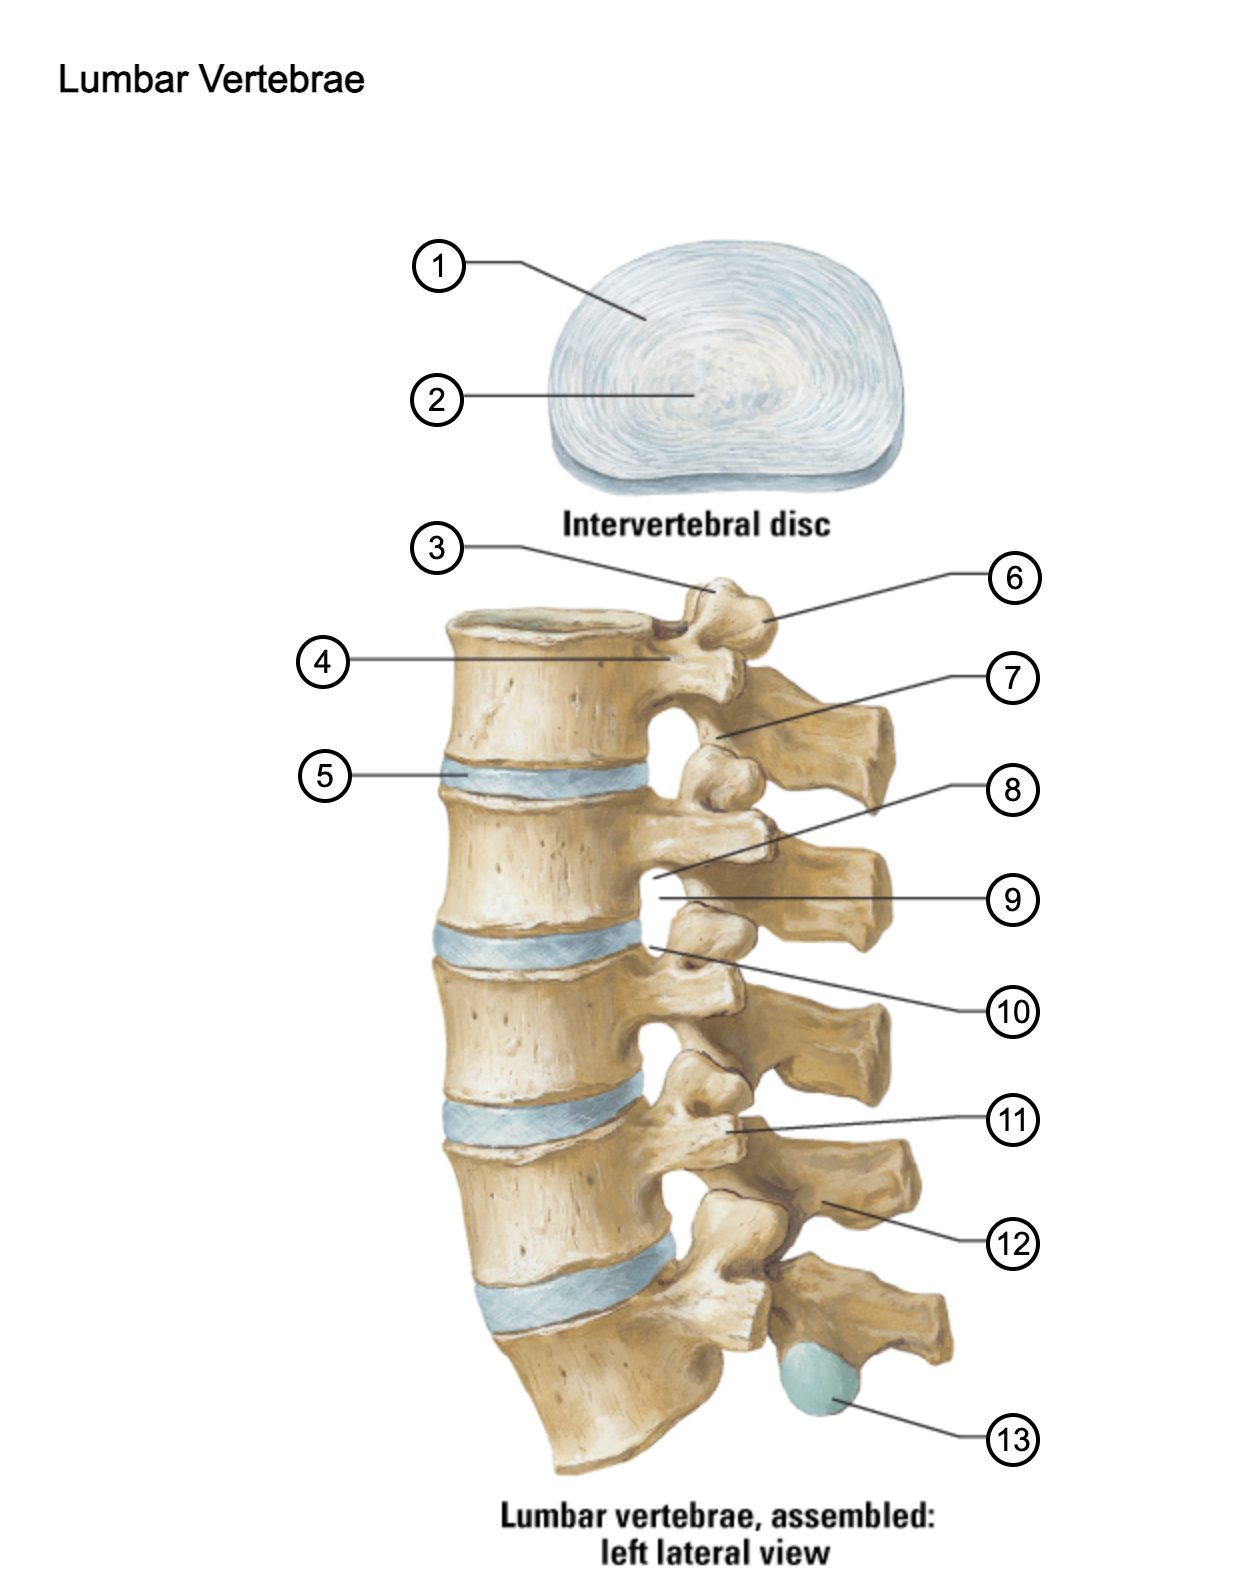

1

anulus fibrosus

2

nucleus pulposus

3

superior articular process

4

pedicle

5

intervertebral disc

6

mammillary process

7

inferior articular process

8

inferior vertebral notch

9

intervertebral notch

10

superior vertebral notch

11

transverse process

12

lamina

13

inferior articular facet